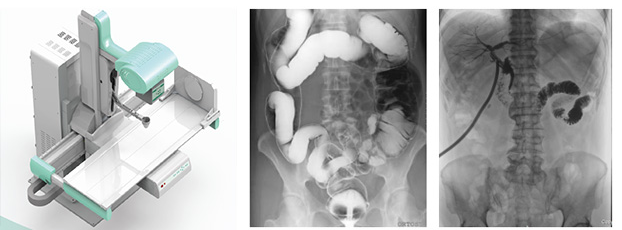

动态DR是一款多功能DR,能够数字拍片、数字透视、数字造影。

动态DR具有大幅面(17inch×17inch)高清拍片、大幅面(17inch×17inch)透视、视频实时保存回放、可视化造影、毫秒级点片等基础功能,以及断层融合、数字减影等延展性功能。

普爱医疗作为全球较好的数字影像设备供应商,专注于DR系列产品的技术创新,在全国范围内率先推出动态DR。以其“一机多用”集常规拍片、胃肠、透视、造影于一体的多功能作用深受放射科临床医生的钟意。